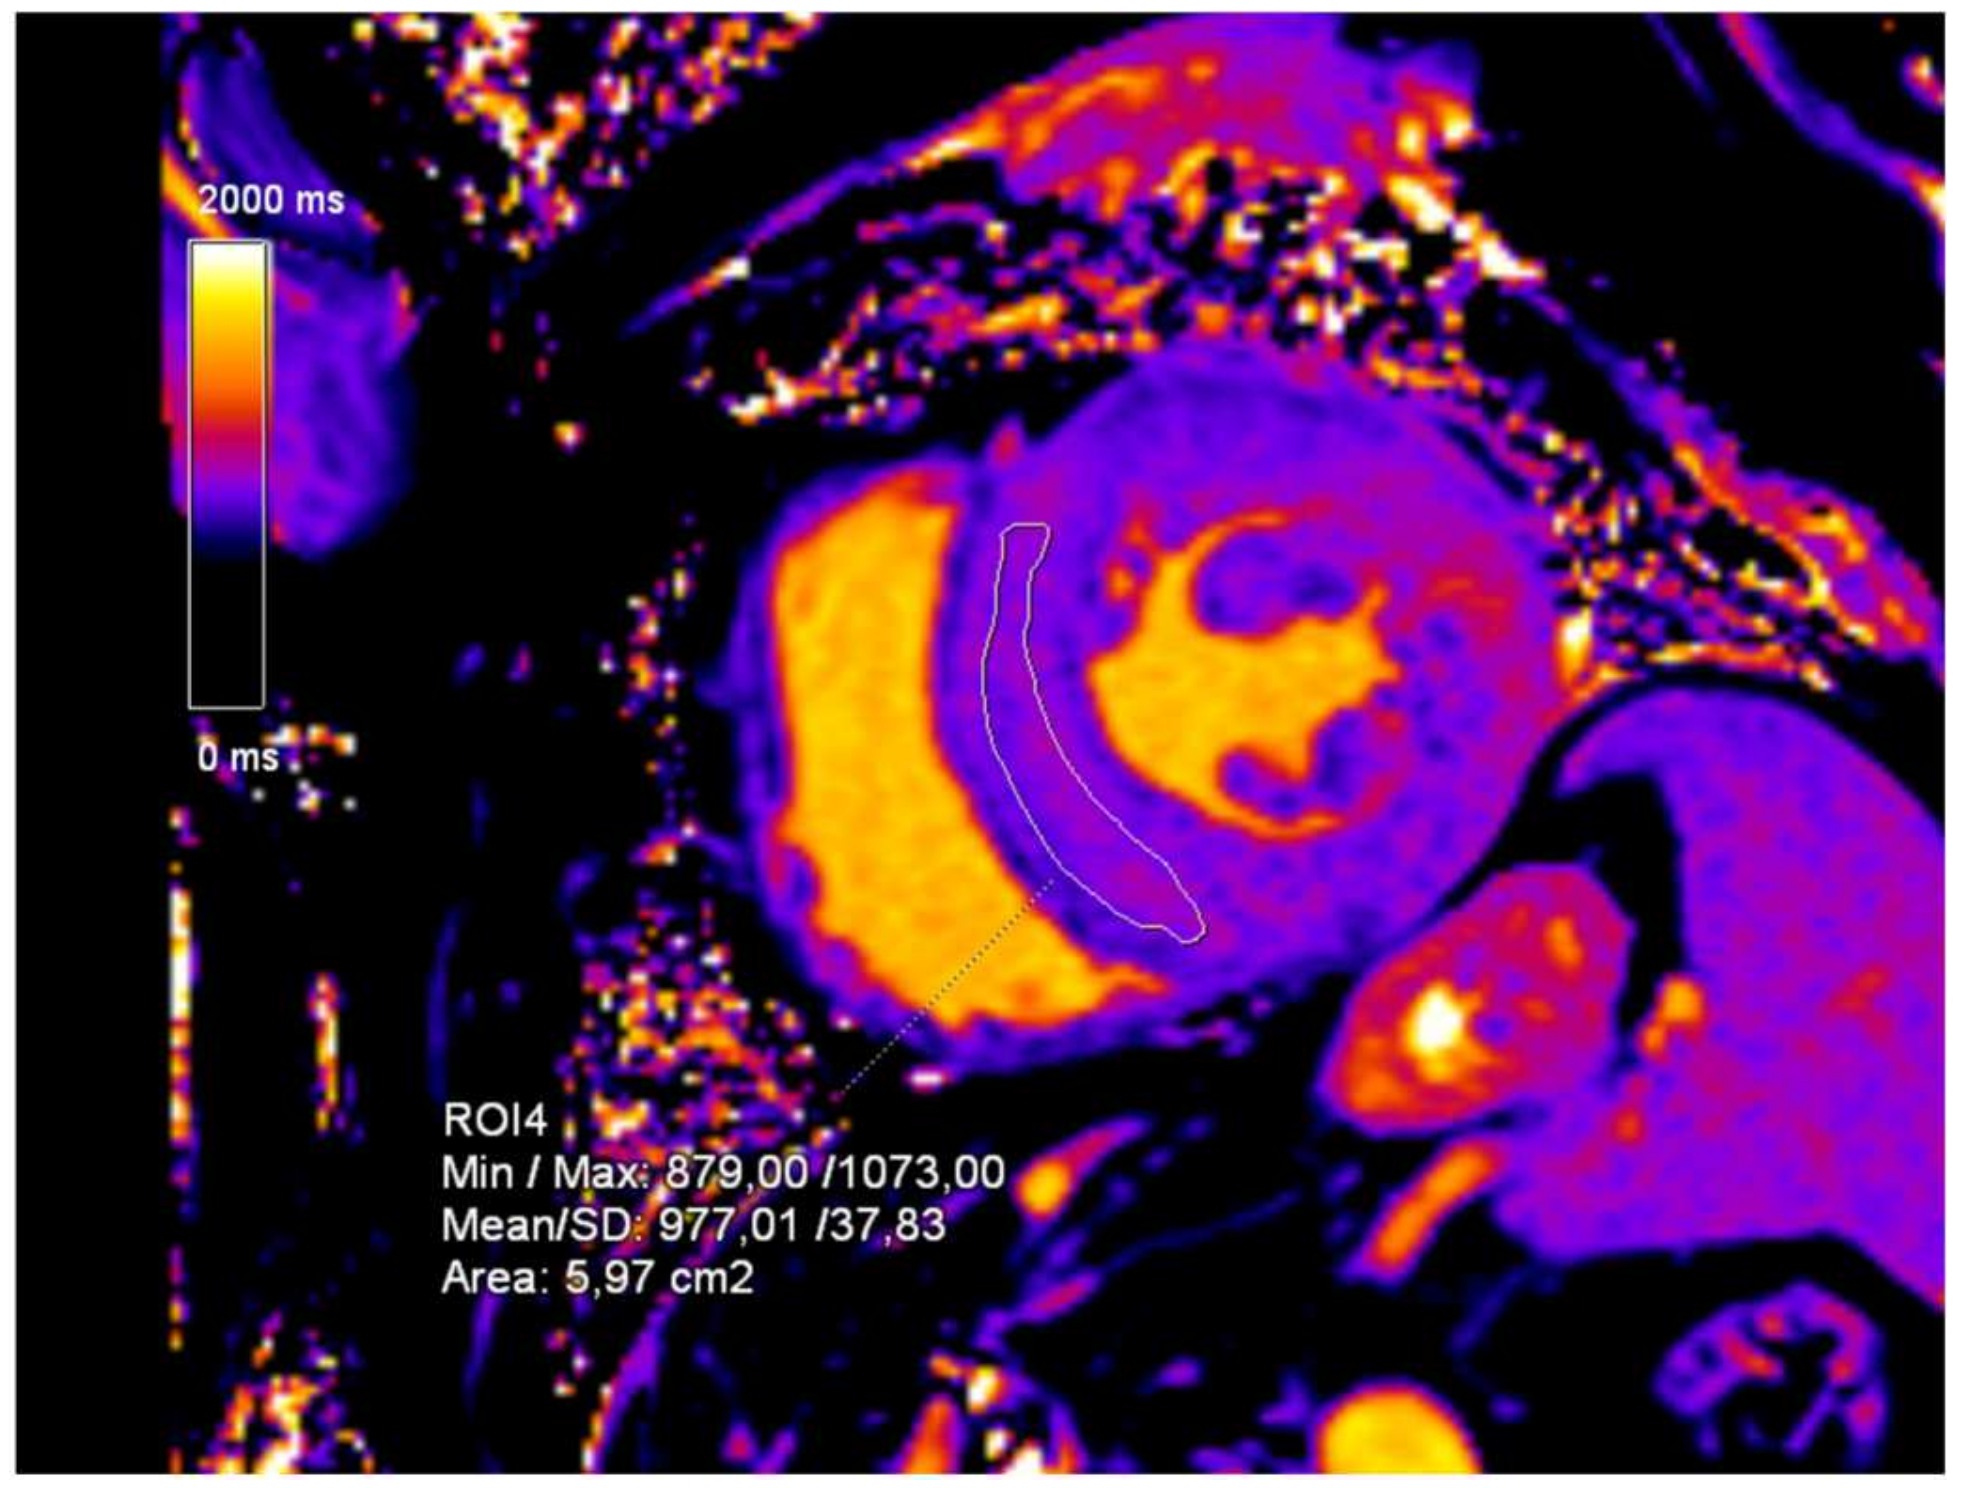

2. Case Presentation